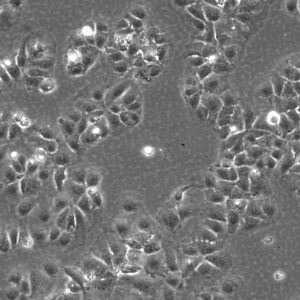

Morphology: Epithelial-like

Growth Properties: Adherent

Description: HuH7 was established in 1982 by Nakabayashi et al. from a 57-year-old Japanese male with well differentiated hepatocellular carcinoma.